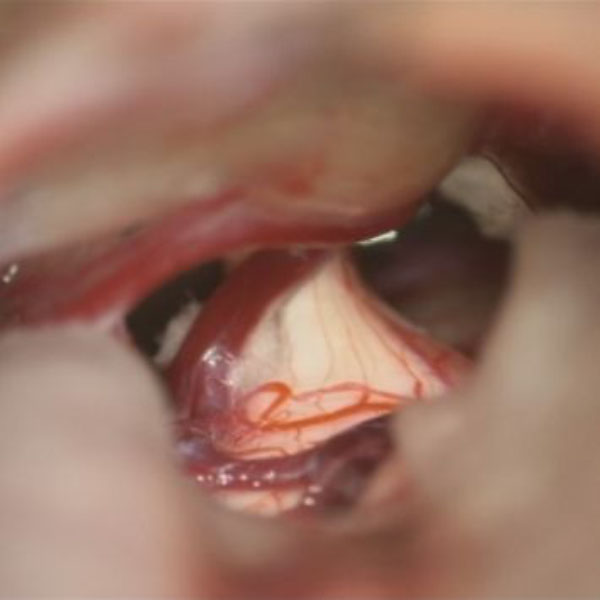

手術中

処置前

処置後